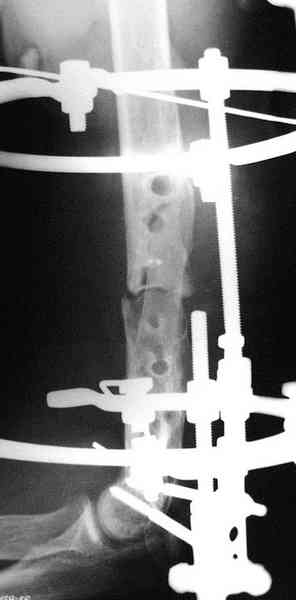

Второй случай, также после множественных операций:

пластина, аппарат, серкляж и парез нерва.

Также ревизия, из-за низкого состояния доступ был

сделан через остеотомию локтевого отростка.

Ложный сустав фиксирован двумя локинг плейт с

аутокостной пластикой, также через два месяца увидели признаки консолидации.

Движение в суставе разрешили в две недели.